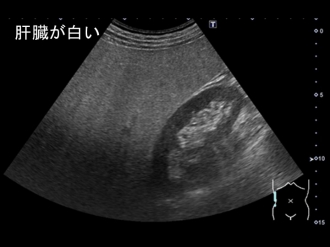

正常肝

脂肪肝